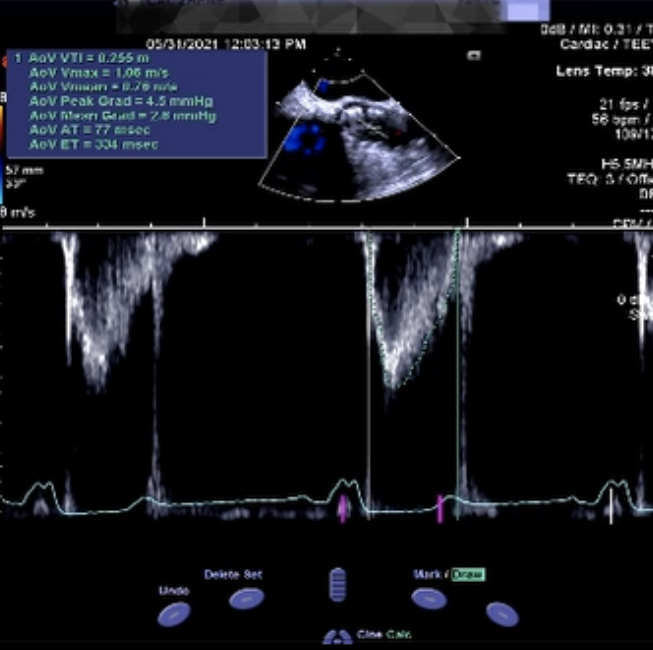

术前术后超声对比

术后超声评估影像,平均压差2.8mmHg,最大流速1m/s,无反流